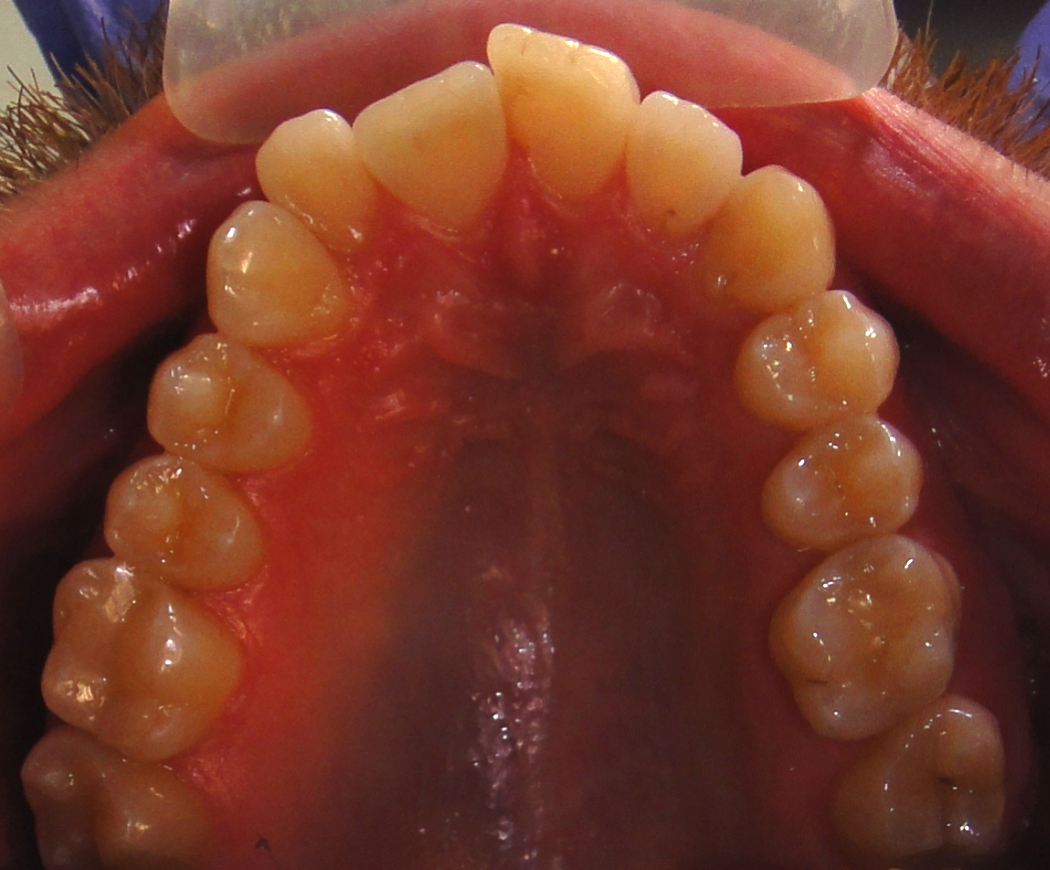

верхняя челюсть

На верхней челюсти мы видим смещение боковых зубов вперед (на фото правая сторона). У этого пациента так произошло по причине раннего удаления молочных зубов, что привело к тому, не поместился клык, 25 зуб прорезался в повернутом положении, а центральный и боковой резцы ушли в сторону.

На фото можно увидеть, что зубы правой и левой сторон не симметричны друг другу - правая сторона более скучена, зубы прижаты друг к другу, уходят вперед, так как с этой стороны выраженный дефицит места.